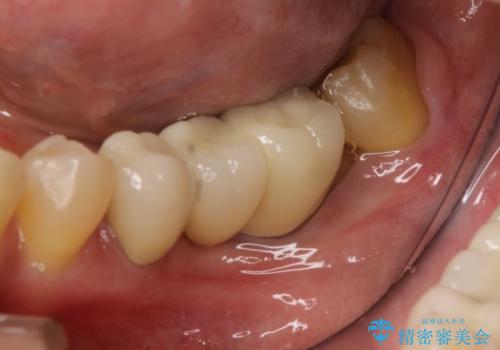

最初にもともとのブリッジを壊し、矯正用の仮歯にかえた上で部分矯正を開始しました。

部分矯正期間はだいたい3か月弱です。

矯正終了後、左下7の近心は再度クリーニングを行っています。

その後ブリッジの製作を行いました。